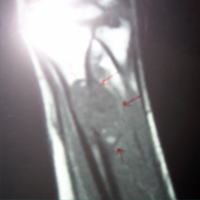

MRI-AP View

Trauma Surgeon in Ahmedabad|Joint Replacement

MRI